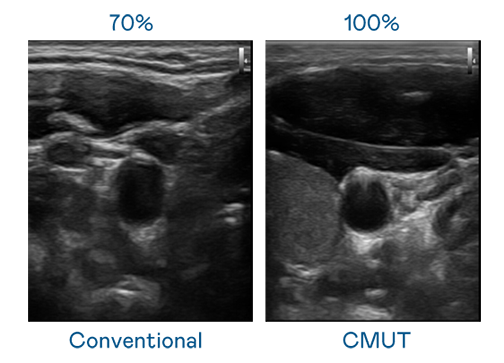

CMUT 技术是一种用电容式微机电元件来产生超音波讯号的技术。与传统 PZT 压电式技术相比,CMUT 频宽增加 30%,更宽频的超音波讯号让影像解析度大幅提升,是实现高影像品质医疗超音波扫描、促进精准医疗发展的关键技术。

大频宽带来超清晰影像

超音波影像的解析度高低,首先取决于探头能发出的讯号频宽。AG贵宾会 CMUT 可提供高清晰的超音波讯号,提供高频宽、高灵敏度、影像纹理细节更高的超音波影像,协助医护人员缩短影像判读时间及利用精准的医疗影像进行诊断。